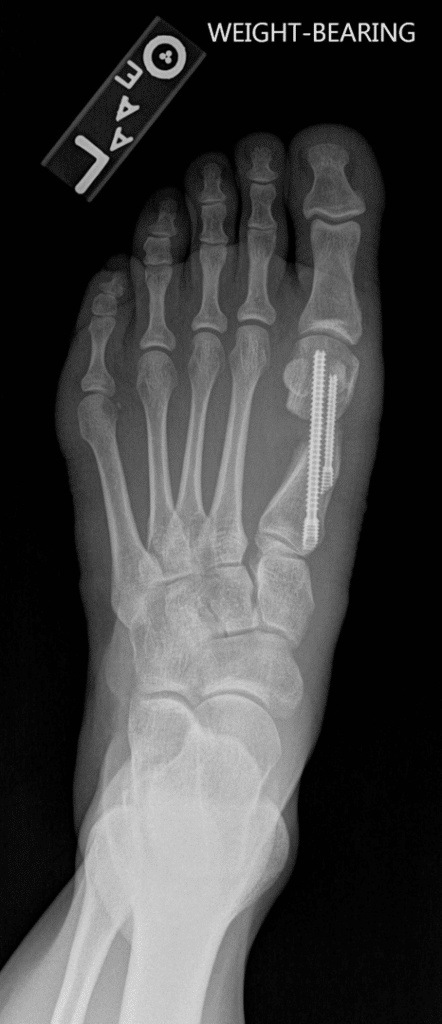

The common operative treatments of bunions involve bony correction through cuts of bone and fixation with screws as well as release of tight tissue structures and tightening of loose ones. Many operations for bunions have been tried over the years with varying levels of success. Techniques often vary from patient to patient depending on anatomy and bony alignment as well as soft tissue laxity.

More modern techniques involved smaller incisions and the use of specialised burrs and screws to minimise tissue damage. Several options for the different presentations of bunions exist and a discussion of the right techniques for your condition is required.

The metalwork used for fixing the bones may occasionally need to be removed. Recovery times and swelling vary from patient to patient.